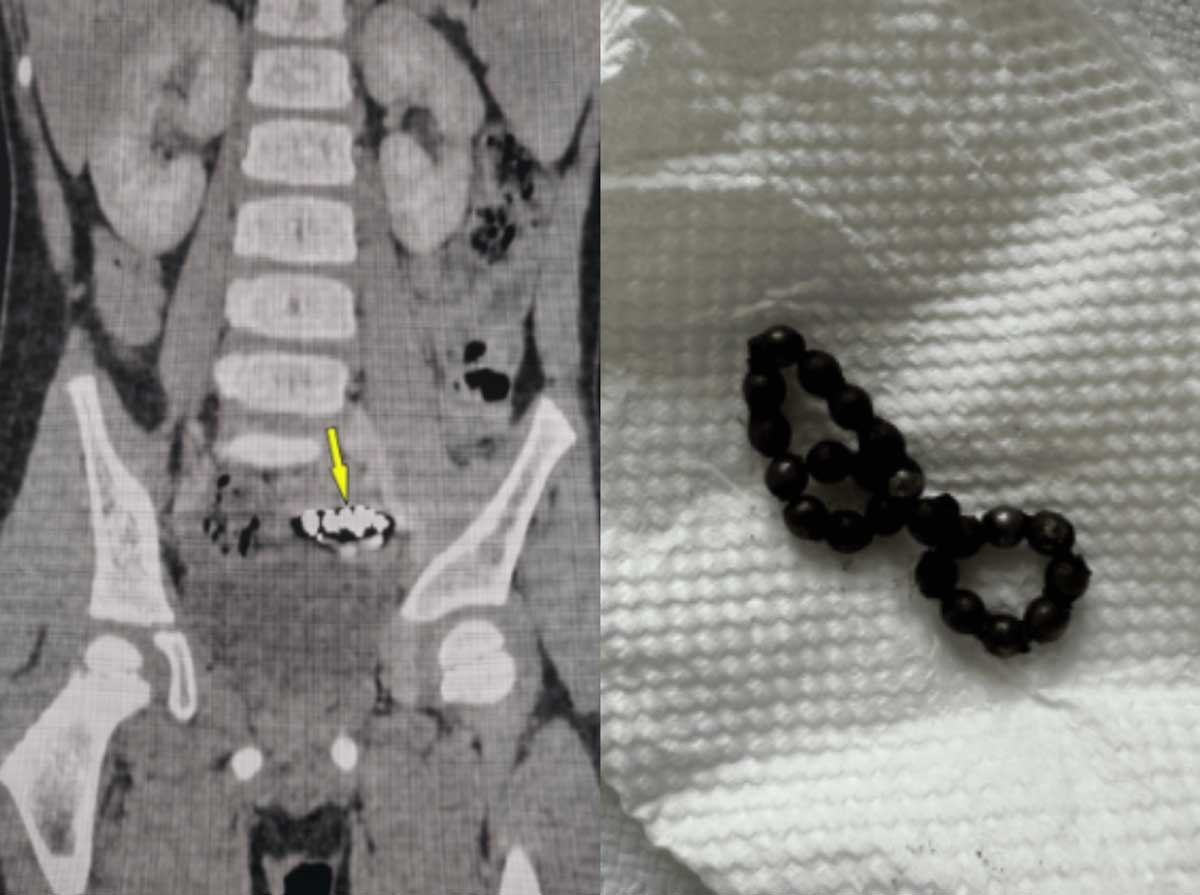

¿À¸¸ ¼ÒÇϸ£ º´¿ø ¼Ò¾Æ°ú ÀÇ·áÁø¿¡ µû¸£¸é, 4¼¼ ³²¾Æ°¡ 1³â°£ Áö¼ÓÀûÀÎ º¹ÅëÀ» °Þ¾ú´Ù. Ãʱ⿡´Â ´Ü¼ø º¯ºñ·Î ÆÇ´ÜµÅ °ü·Ã Ä¡·á¸¦ ¹Þ¾ÒÁö¸¸, Áõ»óÀÌ È£ÀüµÇÁö ¾Ê¾Ò´Ù. ÀÌ¿¡ Ãß°¡·Î ¿¢½º·¹ÀÌ °Ë»ç¸¦ ¹Þ¾Ò´Ù. ±× °á°ú, ÇϺ¹ºÎ¿¡ µ¿±ÛÇÑ À̹°ÁúÀÌ ¿©·¯ °³ ºÙ¾î ÀÖ´Â °ÍÀ» È®ÀÎÇß´Ù.

ÀÌ¿¡ ÀÇ·áÁøÀº º¹°°æ ¼ö¼úÀ» ÁøÇàÇß´Ù. ¹è¿¡ ÀÛÀº ±¸¸ÛÀ» ³½ ÈÄ Ä«¸Þ¶ó¿Í ¼ö¼ú µµ±¸¸¦ ³Ö´Â ¼ö¼ú·Î, ÃâÇ÷À̳ª ÈäÅͰ¡ »ó´ëÀûÀ¸·Î Àû´Ù. ½º¹°µÎ °³ÀÇ ÀÚ¼®ÀÌ ¹ß°ßµÆ°í, ¼·Î ºÙ¾î ÀÖ´Â »óÅ¿´´Ù. ÀÌ·Î ÀÎÇØ Àå ÀϺΰ¡ ±«»çµÅ ¼ÒÀå ÀϺθ¦ ÀýÁ¦Çß´Ù.